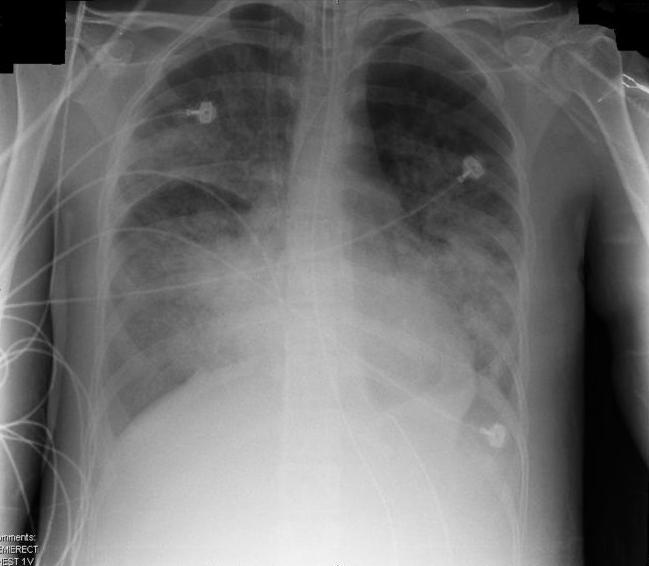

I was transfered to the Intensive Care Unit, intubated, and sedated into a medically-induced coma. From this point, the recollections in the ICU are from my family. After chest x-rays, lab work, and a bronchoscopy with lung biopsy, I was diagnosed with diffuse alveolar damage leading to Acute Respiratory Distress Syndrome, also known as Adult Respiratory Distress Syndrome, or ARDS.

ARDS leads to a buildup of fluid in the air sacs. This fluid prevents enough oxygen from passing into the bloodstream. The fluid buildup also makes the lungs heavy and stiff, and decreases the lungs’ ability to expand. The level of oxygen in the blood can stay dangerously low, even if the person receives oxygen from a breathing machine (mechanical ventilator) through a breathing tube (endotracheal tube). ARDS often occurs along with the failure of other organ systems, such as the liver or the kidneys.